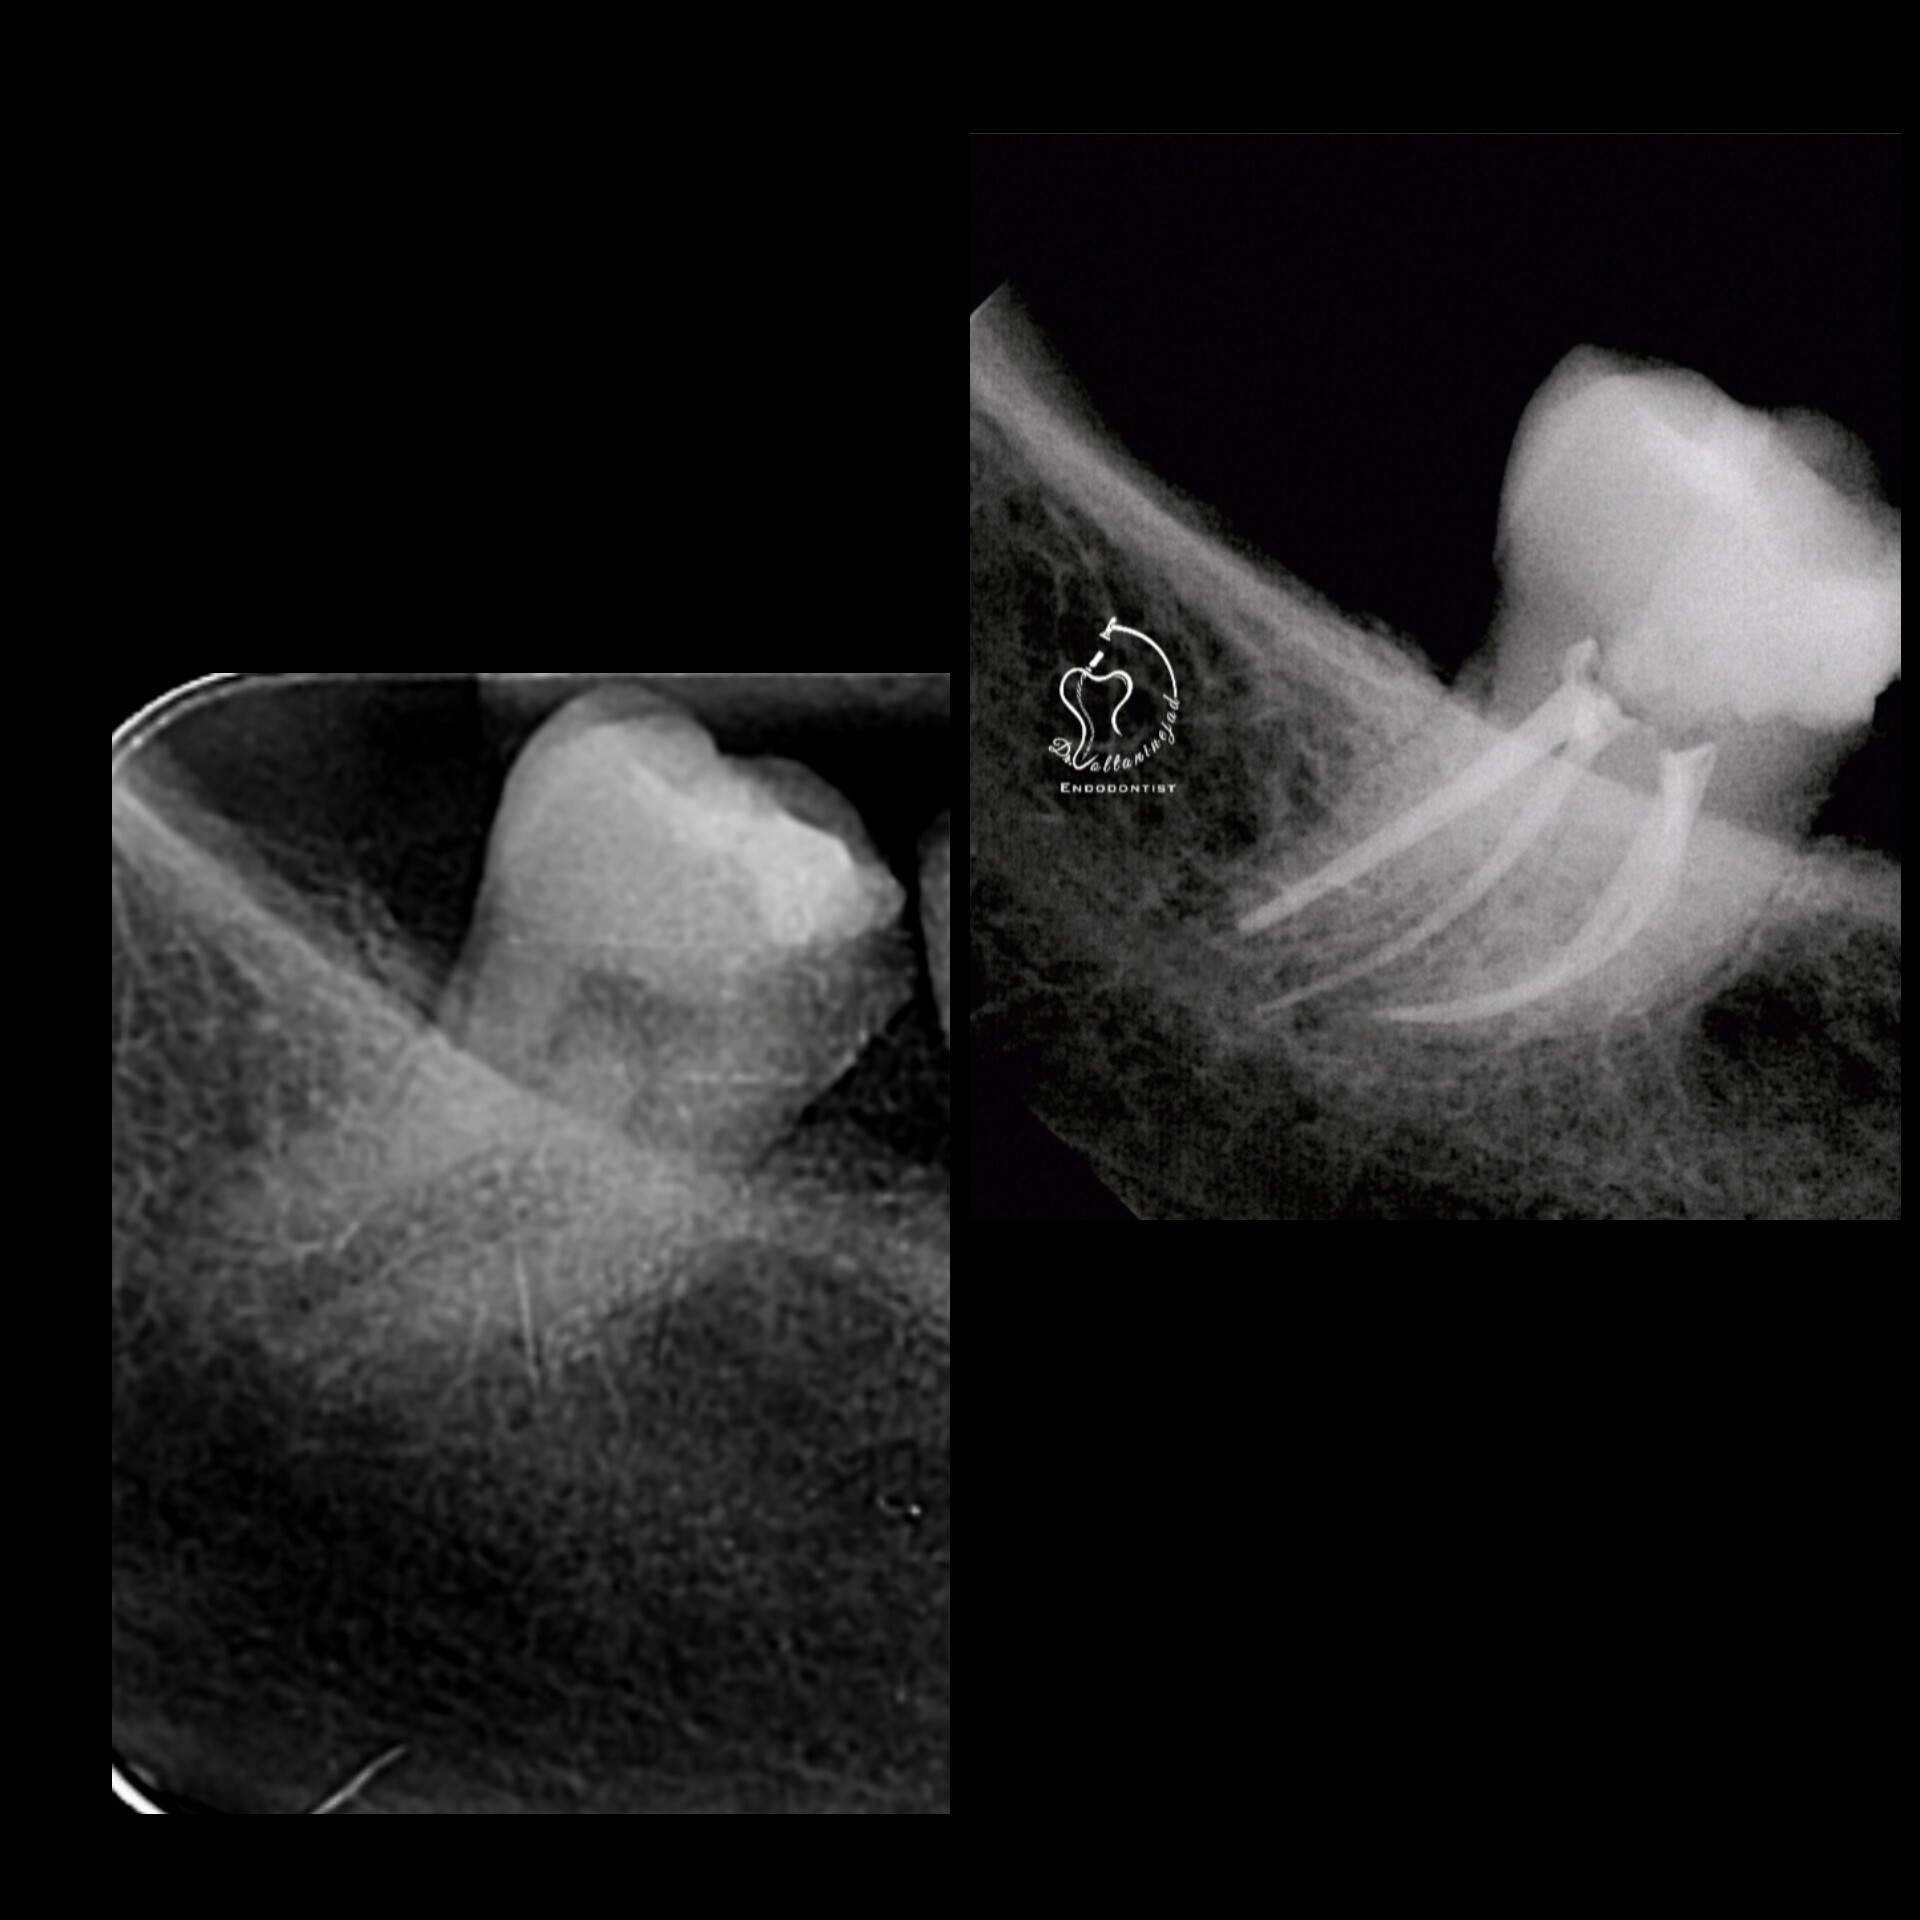

🔹 درمان ریشه دندان با آناتومی نادر

• شرح کوتاه: بیمار ارجاعی با دندان دارای آنومالی (Gemination / دندان دوتایی) که درمان ریشه تخصصی میکروسکوپی با موفقیت انجام شد.

• نتیجه: رفع درد و حفظ دندان به مدت طولانی.

درمان ریشه دندان نادر